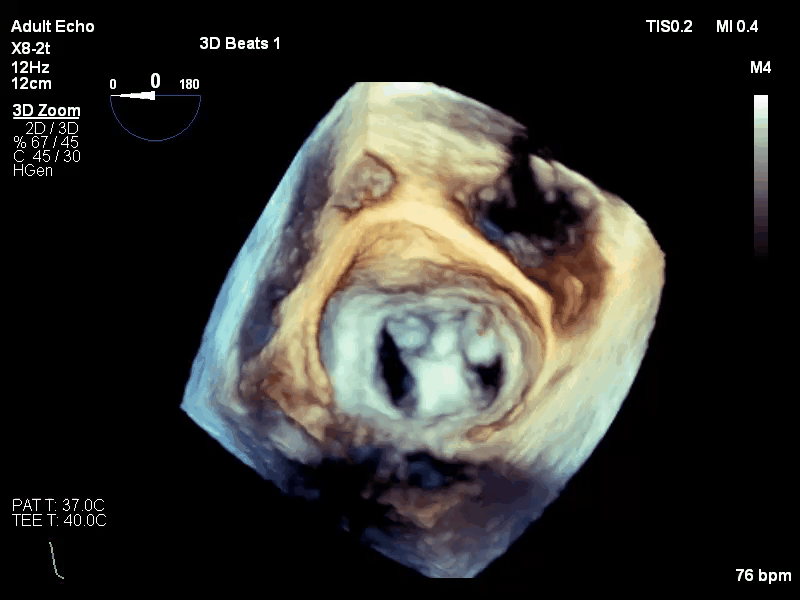

术前评估:

Carpentier II,DMR,二尖瓣P2区域腱索断裂导致极重度二尖瓣反流,累及P1区,心脏扩大,脱垂宽度和间隙较高,瓣口面积5cm²,2区前叶长23mm,后叶长20mm。反流束来自于2区及1区,呈偏心性,沿前叶走行,EROA=0.39cm² (r=0.9cm, av=0.31cm/s, pv=4.0m/s),VC 0.83cm。PGmean 1mmHg,TR 2+。房间隔穿刺空间约5cm。

手术过程:

手术于全麻下进行,采用股静脉房间隔途径,房间隔穿刺后置入外径22F导管鞘及夹合器输送系统,在TEE引导下,将1枚长宽型号的KoKaClip®夹合器顺利植入到二尖瓣2偏1区,夹合器位置稳定。彩色多普勒超声未见明显残余反流,肺静脉多普勒波形由反向恢复正常。多切面证实夹合组织充分,双孔化形成,遂移除器械输送系统,移除后夹合器活动度小,手术顺利完成,患者已于近日出院,出院超声复查良好。

术前

释放后